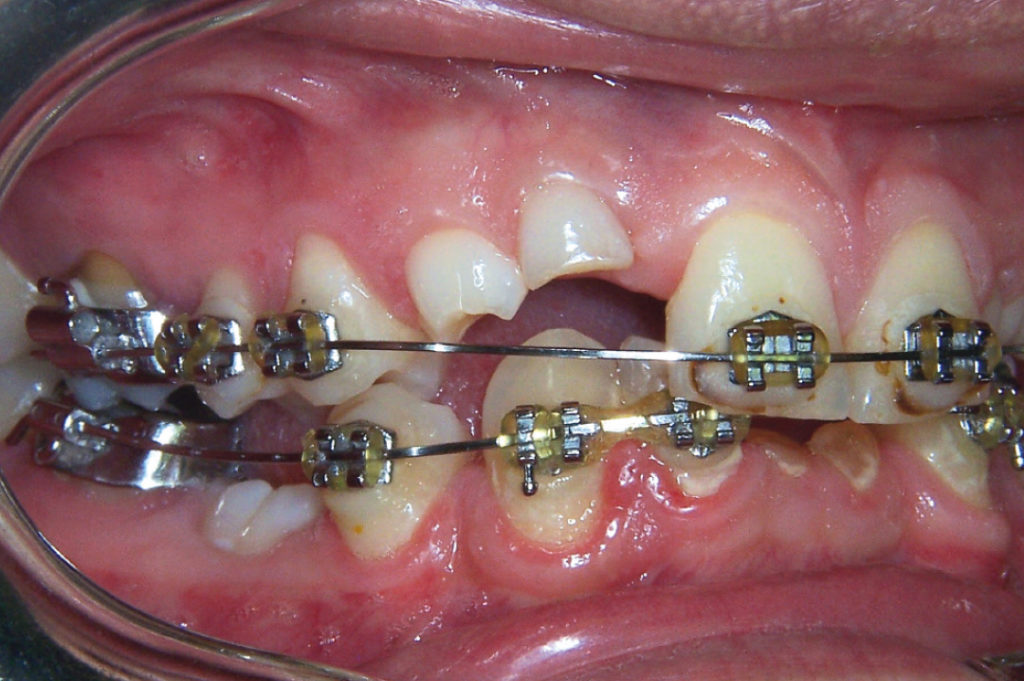

Clinical situation after orthodontic treatment

View of right upper and lower quadrants after orthodontic treatment

View of left upper and lower quadrants after orthodontic treatment